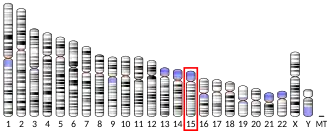

Fibrillin-1 is a protein that in humans is encoded by the FBN1 gene, located on chromosome 15.[5][6] It is a large, extracellular matrix glycoprotein that serves as a structural component of 10–12 nm calcium-binding microfibrils. These microfibrils provide force bearing structural support in elastic and nonelastic connective tissue throughout the body. Mutations altering the protein can result in a variety of phenotypic effects differing widely in their severity, including fetal death, developmental problems, Marfan syndrome or in some cases Weill-Marchesani syndrome.

FBN1 is a 230-kb gene with 65 coding exons that encode a 2,871-amino-acid long proprotein called profibrillin which is proteolytically cleaved near its C-terminus by the enzyme furin convertase to give fibrillin-1, a member of the fibrillin family, and the 140-amino-acid long protein hormone asprosin.[7][8]

FBN1 is a gene approximately 200kb and is made up of a large coding sequence divided into 65 exons located on chromosome 15. This gene encodes for Fibrillin-1 protein.[17] Fibrillin-1 is a large cysteine rich-glycoprotein approximately 350 kDa mainly composed of tandemly repeating domains of epidermal growth factor (EGF)-like modules. These domains are homologous to calcium binding epidermal growth factor module (cbEGF-like motifs) and of distinct 8-cysteine modules to make up elastic and non-elastic tissue.[18][19] These elastic and non-elastic tissues are microfibrillar bundles, heteropolymers of both Fibrillin-1 and fibrillin-2.[20] Elastogenesis is a biological process where microfibrils and elastic fibres are self-assembled via organised deposition by several macromolecules.[21] Polymerised fibrillins can be characterised by their ‘beads-on-a-string’ microfibril structure; giving rise to a microfibril lattice via lateral communication of the individual polymers and structural components.[21]

MFS is caused by a mutation in the FBN1 gene positioned at chromosome 15q21.1 resulting in a deconstructed form of Fibrillin-1.[5] Fibrillin-1 is a 350-kDa, 2871-amino acid cystine-rich glycoprotein that is responsible for the amalgamation of elastin into the elastic fibres of the connective tissue in the extracellular matrix (ECM).[27][28] The fragility of the connective tissue usually results in aortic aneurysms due to the wall having the inability to withstand intraluminal pressure.[29] Defects in fibrillin-1 results in elevated TGF-β levels that directly correlate to MFS.[29]